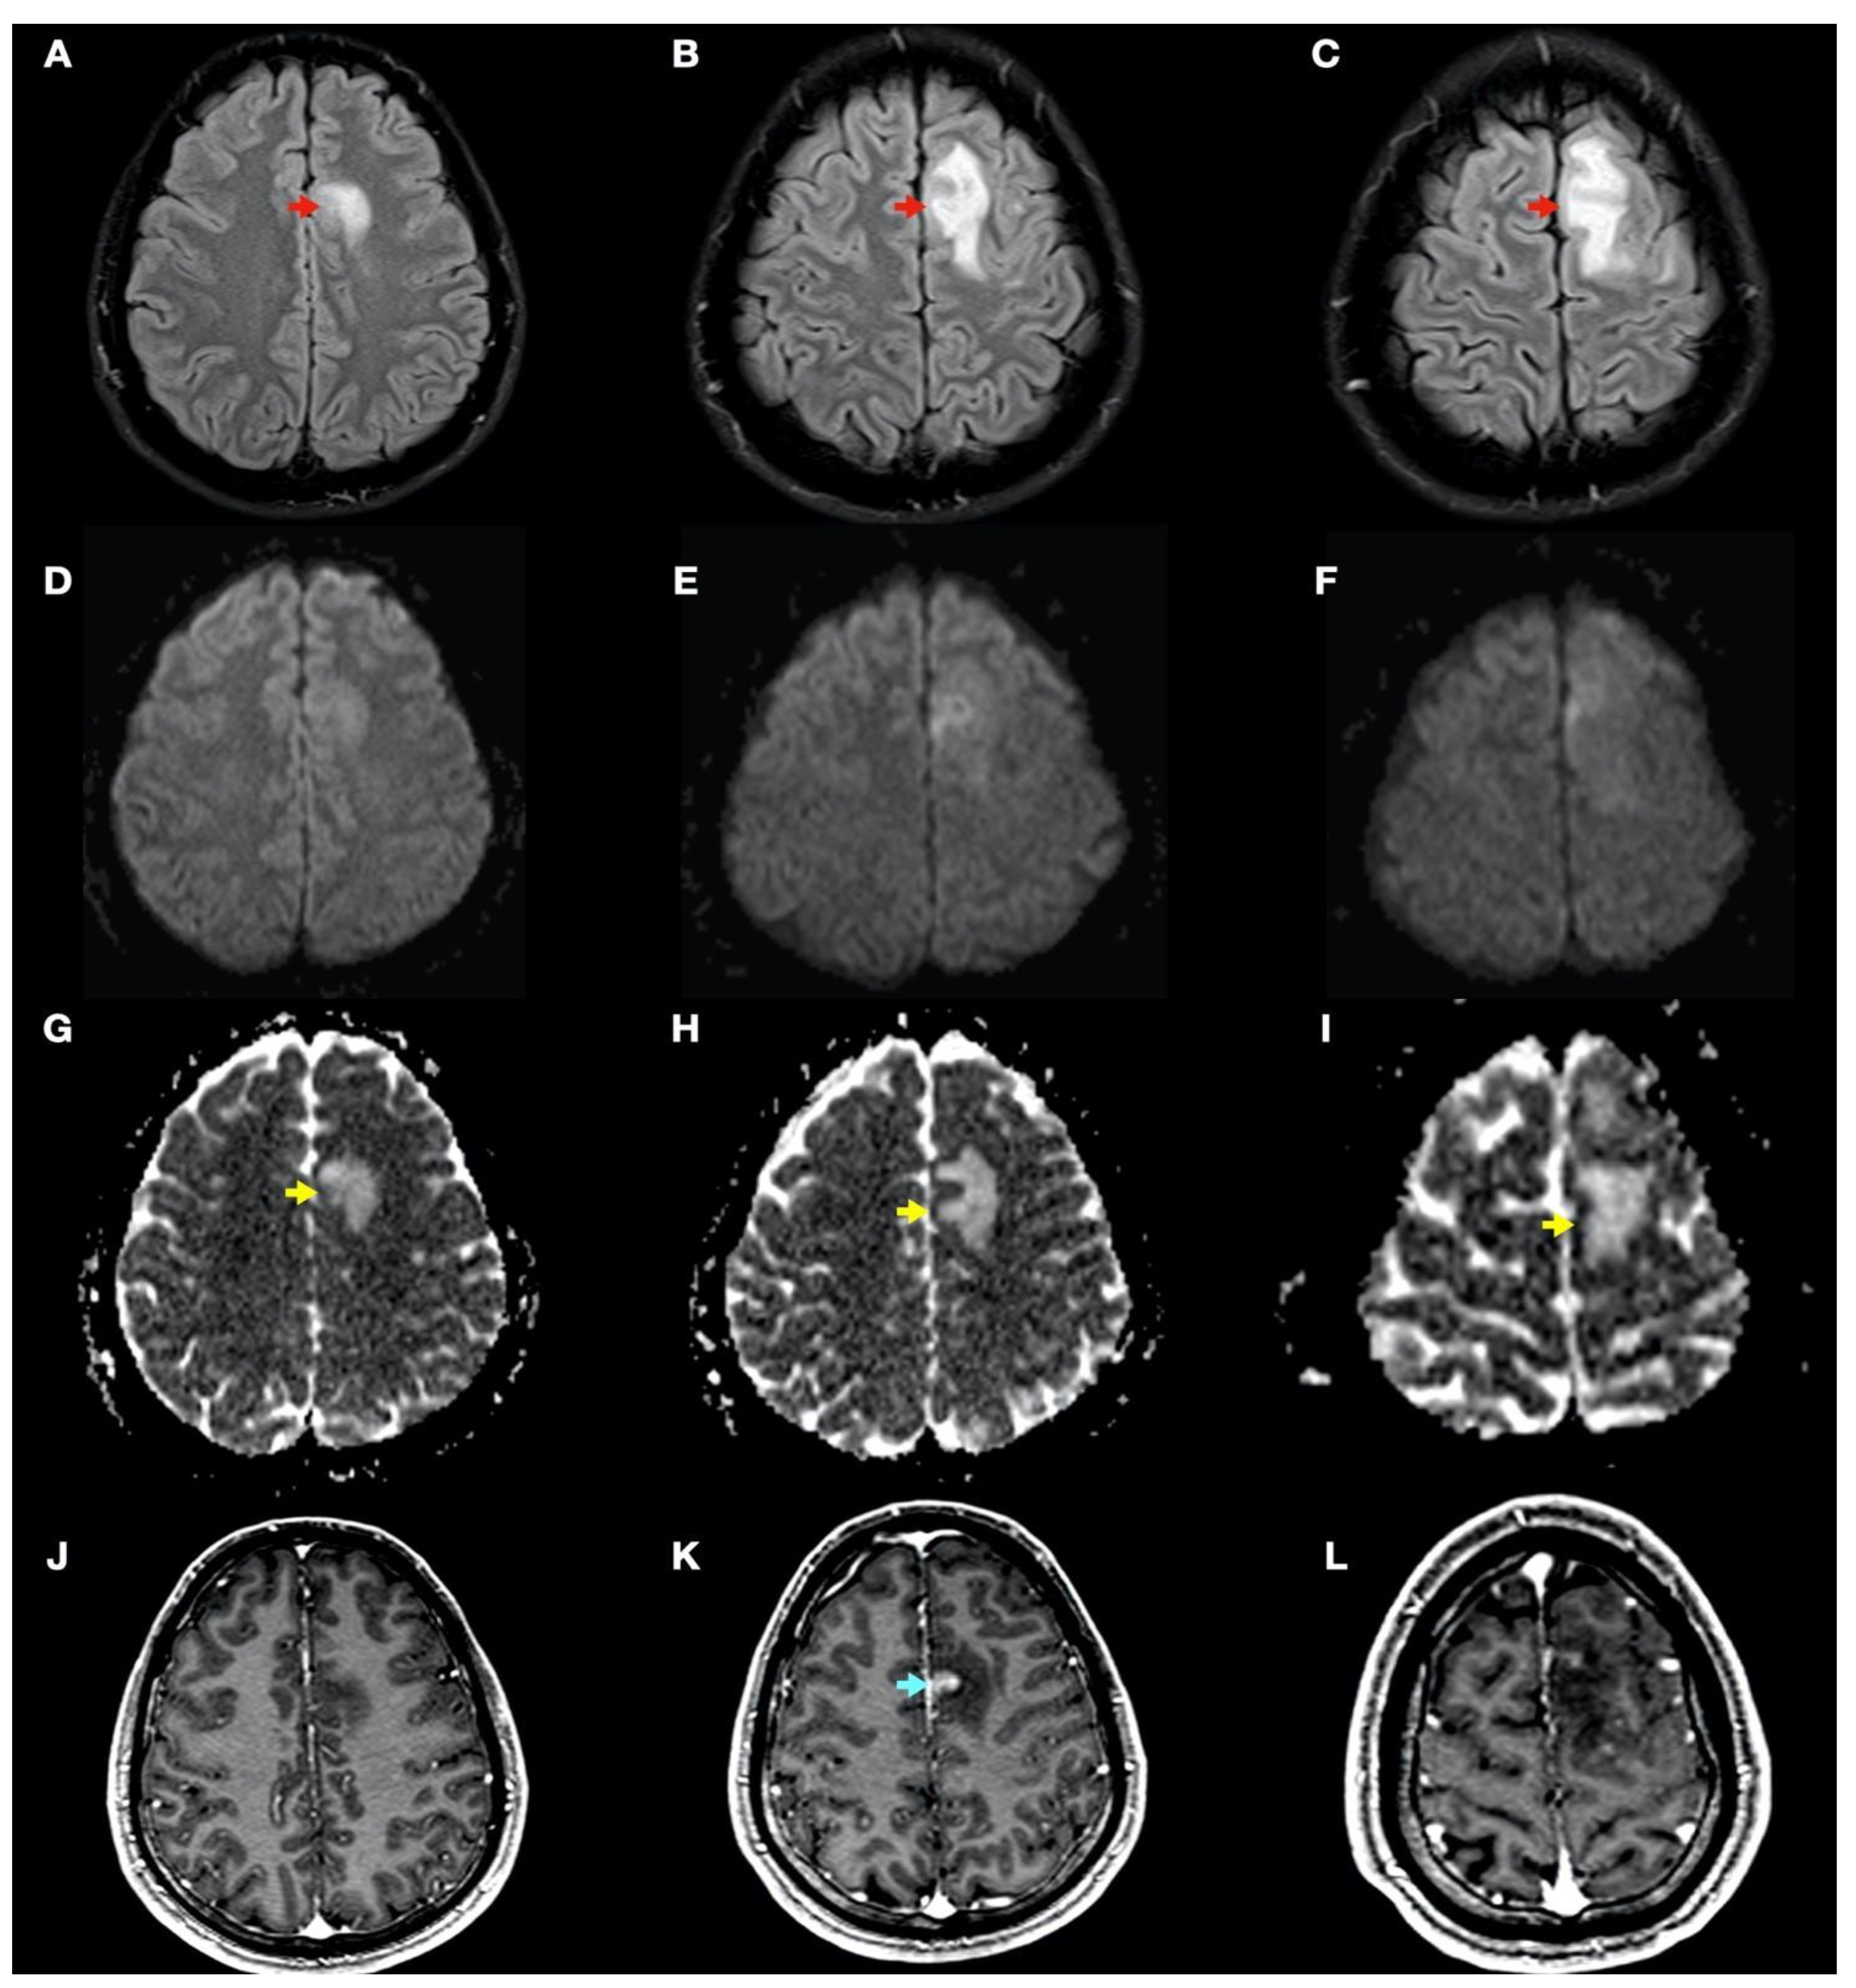

During admission, the following complementary examinations were performed: brain magnetic resonance imaging (MRI; Figure 3, Figure 4 and Figure 5) showed right temporal and left frontal cortico-subcortical lesions, probably secondary to neurological involvement of DCS; neurosonological study of supra-aortic and intracranial arteries showed no atheromatosis or significant hemodynamic alterations; blood tests, including biochemistry, hemogram, coagulation study, serology and autoimmunity, were normal; transthoracic echocardiography was normal (including negative agitated saline contrast study for right-to-left shunt); and total body CT scan showed no evidence of neoplastic process.

Figure 3.

Brain magnetic resonance imaging (MRI): Images (A–I) from MRI 4 days after clinical onset; images (J–L) from MRI 5 days after clinical onset. Axial fluid-attenuated inversion recovery (FLAIR) images (A–C) show a left frontal cortico-subcortical hyperintense lesion (red arrows), also observed in other long-time repetition (TR) sequences (e.g., T2-weighted and proton density sequences). Axial diffusion-weighted imaging (DWI) (b1000) sequences (D–F) did not show a high signal intensity of lesions, whereas axial apparent diffusion coefficient maps (G–I) show a hyperintense lesion in this location (yellow arrows). (J–L) Axial gadolinium-enhanced 3D T1-weighted imaging (Gd T1WI) shows the presence of different areas of enhancement with irregular morphology (blue arrow), not suggestive of tumor enhancement.

In this complex scenario, we report an uncommon case of DCS in a spearfishing breath-hold diver. The diver had a high-risk dive profile, with repetitive breath-hold dives to a maximum depth of about 30 m for several hours and short surface intervals. He had a good response to hyperbaric chamber treatment (US Navy Table 6) and was clinically asymptomatic. Neuroimaging findings showed hyperintensity in long-TR sequences (FLAIR, T2WI), as well as in ADC mapping, and no hyperintensity in DWI sequences, compatible with the presence of vasogenic edema in the left frontal and right temporal lobes (Figure 3 and Figure 4). Regarding MRI perfusion, in the contrast enhancement area, there was an increase in cerebral blood volume (CBV) in relation to the contralateral side and normal subcortical white matter. In the average curves, the area under the curve was higher in the enhancement zone than in the other two zones, which would indicate an increase in perfusion (Figure 5). Initially, given the atypical nature of the lesions, with irregular enhancement in T1WI with intravenous contrast (although their radiological characteristics were not suggestive of neoplastic etiology) [22,23], an extension study with body CT was completed, showing no presence of neoplasia. Likewise, prior to the neuroimaging study, a vascular study (neurosonological, echocardiographic) was performed, as was an extensive blood test study, with no pathological findings. The radiological evolution of the lesions tended towards resolution, with minimal chronic lesions persisting, compatible with small areas of cerebral malacia (Figure 6).

Thus, in our case, the brain lesions found had the typical radiological features of vasogenic edema. This allows us to exclude, in this case, the ischemic nature of the process (e.g., secondary to arterial occlusion), which would show radiological characteristics of acute ischemic injury (cytotoxic edema) in one or more cerebral vascular territories, as well as a reduction in CBV in MRI perfusion maps. The findings of the radiological evolution contributed to this. Follow-up MRI demonstrated complete resolution of the FLAIR/T2WI signal abnormalities, confirming reversible vasogenic edema, since cytotoxic edema formation and infarction lead to gliotic lesions in the brain and consequently result in permanent signal alterations (hypersignal in long-TR sequences) [24]. Diffusion-weighted MRI reflects the Brownian motion of water molecules within the tissue, thus providing data on tissue integrity. DWI and ADC mapping have mainly been used for the detection of acute ischemia (cytotoxic edema) and for distinguishing between cytotoxic and vasogenic edema [25]. In addition, the ADC map is an MRI image that shows diffusion more accurately than conventional DWI by removing the T2 weighting that is inherent in conventional DWI.